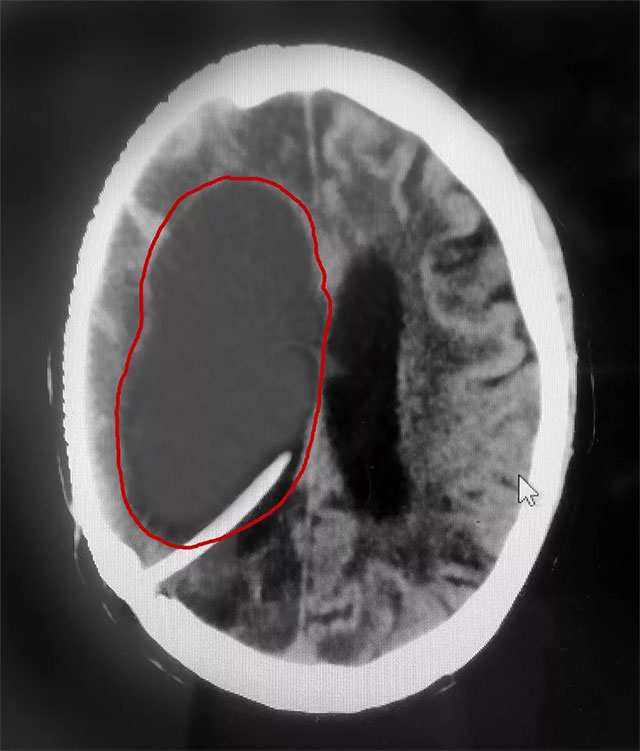

在完善相關(guān)檢查后,患者重度腦積水明確,若不及時治療可能危及生命。

▲ 患者右側(cè)腦室重度腦積水被及時置管分流